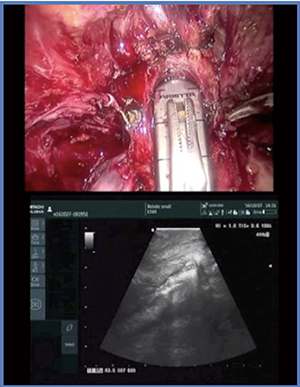

そこで,2016年に登場したのがL51Kである(図1)。L51Kは,L43Kの特長に加え,プローブ先端の長さが25mmと短く,幅も少し細くなり,ケーブルも細くなったため,10mmのトラカールへの挿入も可能である。

図1 小型化された術中エコープローブL51K

症例1は,36歳,男性,右腎細胞がんで,RENAL Nephrometry Score(RNS)は7aである(図2)。腫瘍はやや埋没しており,経腹膜アプローチにてRAPNを施行した。術中エコーを用いて全周のマーキングを丹念に行っていくが,L51Kはケーブルが柔らかく,腫瘍に押し当てながら走査しても把持鉗子から外れることがないため,把持したままストレスなく操作することができる。本症例は切除断端陰性で,出血は少量,阻血時間は19分であった。

図2 症例1:RNS 7aの右腎細胞がん(36歳,男性)

L51Kでは,プローブのサイズが小さくなったことで尖部に当てることが可能となり,形態をきわめて明瞭に描出可能であった(図5)。尖部と括約筋部尿道の処理の際に,形態の個体差の情報をリアルタイムに得られる可能性があり,今後L51Kは,RARPの領域でも威力を発揮するものと期待している。

図5 L51Kによる前立腺尖部の描出